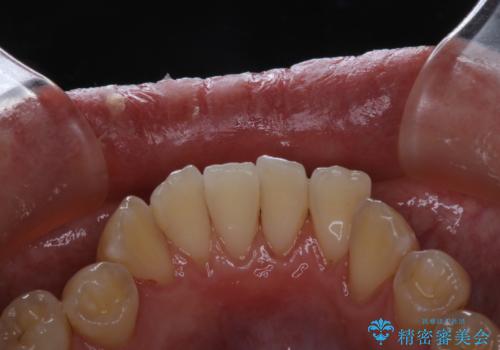

- しばらく、クリーニンングに来れなかったため、全体的な汚れが気になるとのことでした。PMTC60分コースを行いました。

毎日しっかりと歯磨きをしていても、日常生活での飲食物などにより着色してしまうことはあります。PMTCでは歯の表面の凸凹にミネラルを補給しツルツルの状態に仕上げます。定期的に行うことで歯質の強化になり着色が付きにくい状態になります。

普段の飲食物や歯磨き、生活習慣などにより着色の付き具合には個人差があります。どれくらいの頻度で行うことがベストかはその都度担当の歯科衛生士とご相談します。